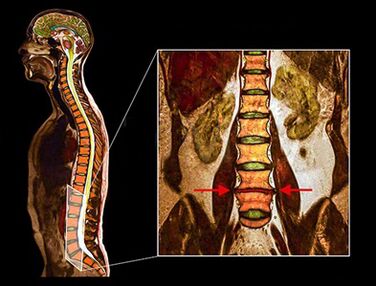

- Οι παραπάνω διαγνωστικές μέθοδοι είναι συνήθως επαρκείς για τη διάγνωση της οστεοχονδρισμού, αλλά η ακριβής διάγνωση απαιτεί τη χρήση μεθόδων απεικόνισης.

- CT

- Ακτινογραφία

- MSCT

- ΕΛΑΦΡΟ ΚΤΥΠΗΜΑ

- MRI - Αυτή η διαγνωστική μέθοδος σάς επιτρέπει να διευκρινίσετε τον βαθμό εκφυλισμού, την παρουσία καταγμάτων, τις κήλες των δίσκων στένωσης. Συχνά μια μελέτη μαγνητικής τομογραφίας είναι απαραίτητη για την προετοιμασία για χειρουργική θεραπεία προκειμένου να προσδιοριστεί με ακρίβεια η θέση του εκφυλισμένου δίσκου και να προγραμματίσει τη λειτουργία.

Μελέτες έχουν δείξει ότι τα αποτελέσματα της μαγνητικής τομογραφίας με μέτριο ή σημαντικό εκφυλισμό δίσκων βρίσκονται όταν σαρώνουν ασθενείς, τόσο με έντονο πόνο όσο και ελάχιστο ή έλλειψη πόνου. Επιπλέον, πολλές οδυνηρές συνθήκες μπορεί να μην εμφανίζονται σε μαγνητική τομογραφία. Για το λόγο αυτό, η διάγνωση δεν μπορεί να γίνει αποκλειστικά με βάση τα αποτελέσματα της απεικόνισης και η επαλήθευση της διάγνωσης είναι δυνατή μόνο με βάση το σύνολο όλων των μεθόδων κλινικής και οργανικής εξέτασης.